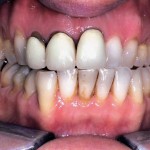

“Interproximally connected flap” nella riabilitazione implanto-protesica

Riassunto

Obiettivi. Illustrare l’utilizzo dell’interproximally connected flap, incisione chirurgica proposta per la correzione di difetti ossei parodontali in settori ad alta valenza estetica, nella riabilitazione implanto-protesica di...